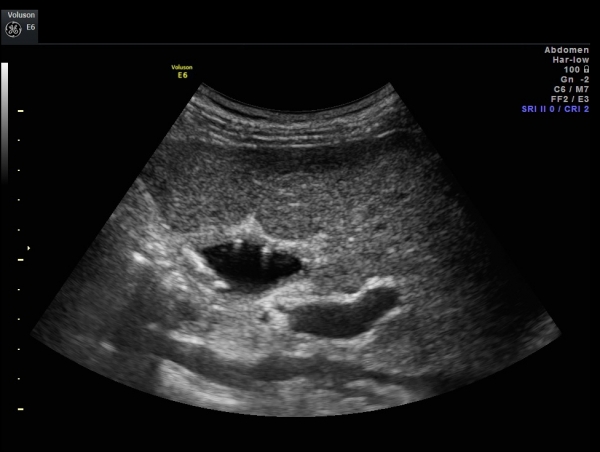

Кстати, в вашем случае, на мой взгляд, нет острого холецистита, судя по размерам пузыря, есть его увеличение. А стенки все мастаки мерить под нужным ракурсом.

Ну тогда и я "согрешу в свое оправдание".

А где здесь мерить будем?

Так где мерить будем в моем примере?